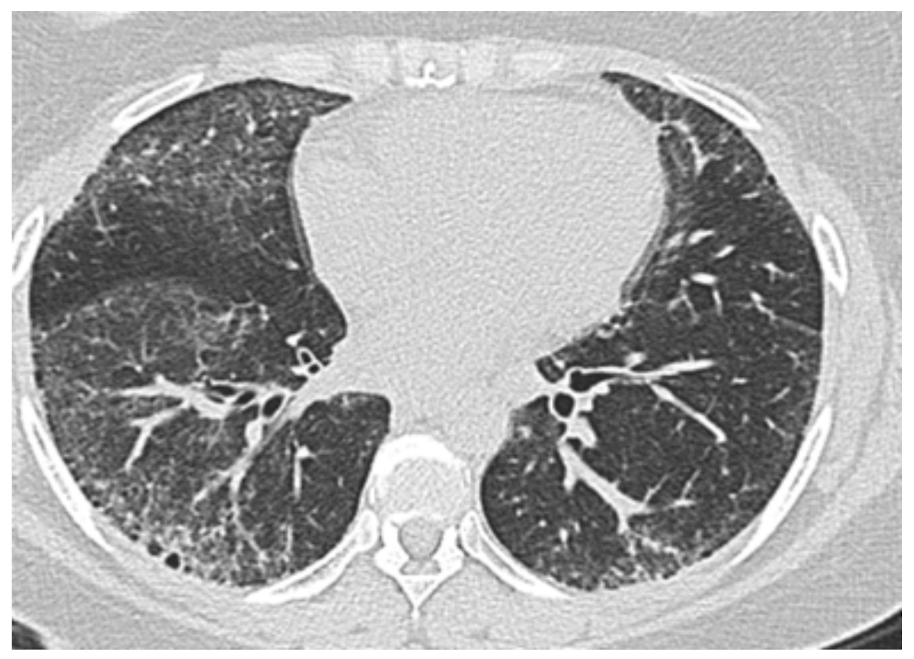

3.2. Interstitial Lung Disease-Associated PH in SSc